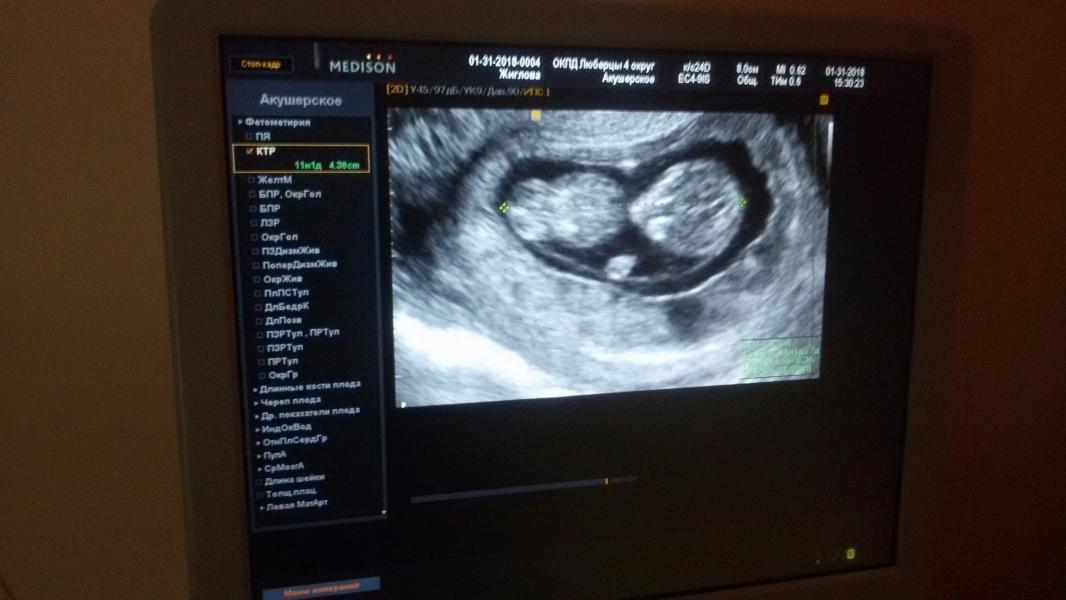

Сегодня был первый скрининг...Ну как - был... Приехала я в Люберцы к 8 утра, дождалась своей очереди и на узи мне говорят - ребенок отвернулся, расшевелить надо. Мол, идите на кровь, затем съешьте что-то сладкое и через полчаса приходите на доосмотр. Сказано -сделано. И что вы думаете? Мало того, что моя козюлина решила спать и никакой глюкозой ее не поднимешь, так еще и во время замеров оказалось, что она у меня совсем маленькая еще и скрининг делать рано((( Я негодую, короче( Единственный плюс...